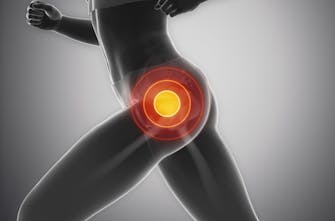

Γιατί είναι σημαντική η εκγύμναση των μυών του ισχίου για τους δρομείς

Όλοι γνωρίζουν πλέον πως οι εκγύμναση των μυών του ισχίου και ιδιαίτερα των πλευρικών μυών του ισχίου έχει μεγάλη σημασία για τους δρομείς τόσο για την βελτίωση της απόδοσης όσο και για την μείωση των τραυματισμών.

ΠΛΕΥΡΙΚΟΙ ΜΥΕΣ ΤΟΥ ΙΣΧΙΟΥ

Στο σημερινό άρθρο θα εξετάσουμε τους πλευρικούς μύες του ισχίου. Οι πλευρικοί μύες του ισχίου είναι η μυϊκή ομάδα στο εξωτερικό του ισχίου και περιλαμβάνουν:

1. Μέσο γλουτιαίο

2. Μικρό γλουτιαίο

3. Τείνον την πλατεία περιτονία.

Ποια είναι η λειτουργία των πλάγιων μυών του ισχίου και γιατί είναι τόσο σημαντικοί για τους δρομείς

Στο τρέξιμο, η κύρια λειτουργία των πλευρικών μυών του ισχίου είναι να σταθεροποιήσουν την άρθρωση του ισχίου καθ 'όλη τη διάρκεια του κύκλου βάδισης.